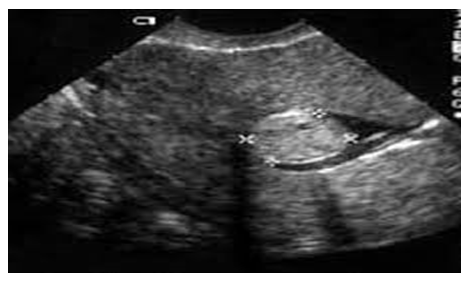

| Figure 6. Patient Kh-va, 49 years old, Record No. 879. Ultrasound revealed a submucous fibroid |